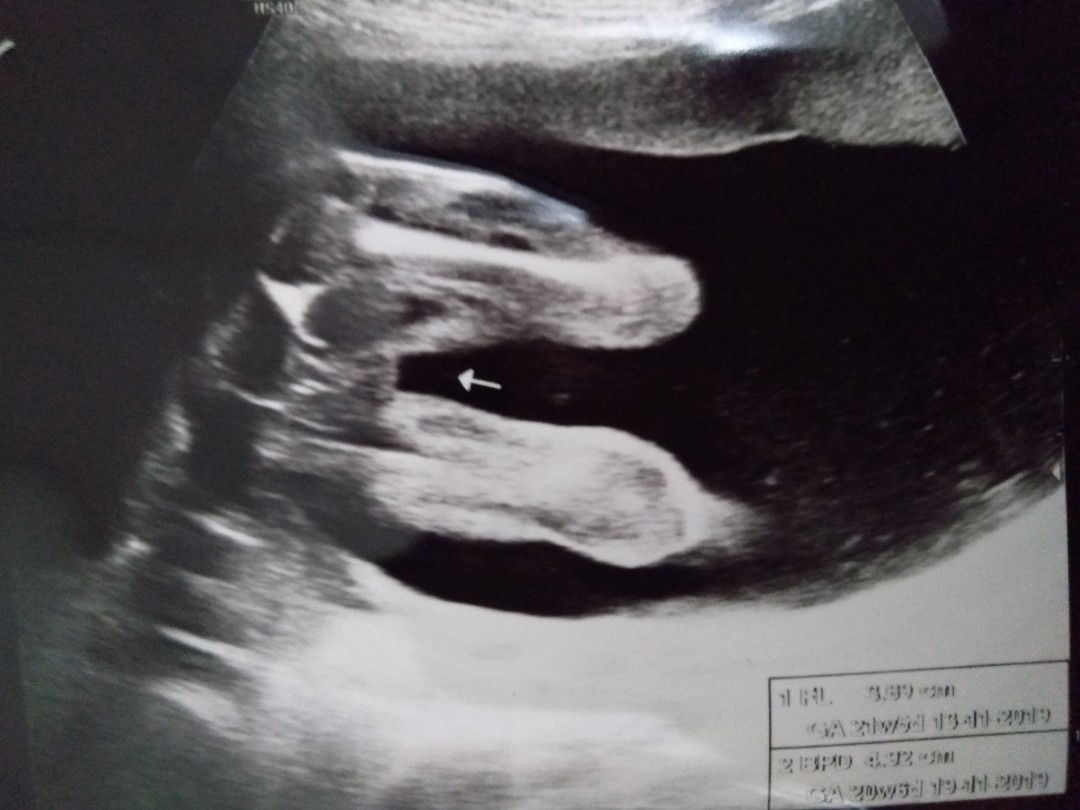

เพศลูก

20สัปดาห์หมอซาวด์เห็นเพศหญิง มีใครซาวตอนช่วงอายุครรภ์ไกล้ๆกันบ้างคะ แล้วชัดเจนรึป่าวคะ พอดีบ้านนี้อยากได้ลูกสาวอยู่แล้ว แต่กลัวไม่ชัดเจน กลัวซาวครั้งต่อไปเห็นจู๋

ซาวด์อายุครรภ์20-21วีค

บ้านนี้คุณหมอซาวตอน18w เห็นเพศหญิงค่ะ สรุปคลอดแล้วก็เพศหญิงค่ะ